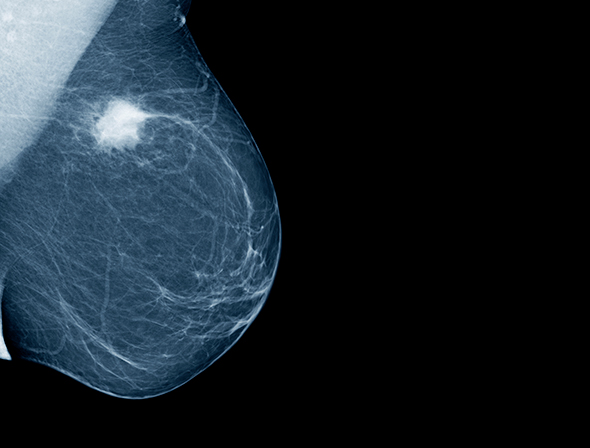

Utredning ved mistanke om kreft bør ikke forsinkes unødig. Vi kan likevel måtte akseptere at terskelen heves. Ved lav mistanke, for eksempel et lite suspekt mammografifunn, kan utredningen trolig utsettes uten at det går vesentlig ut over prognosen. Generelt bør man fokusere på det som er nødvendig for å legge en initial behandlingsplan, og unngå overutredning. Overføring av pasienter mellom sykehus bør unngås om mulig.

Behandling med kurasjonsmål skal prioriteres høyt. De fleste kreftoperasjoner bør gjøres innen korte tidsfrister. Unntak kan være lavrisiko-prostatakreft, små brystsvulster og annet. Internasjonale organisasjoner som American College of Surgeons har foreslått triage av kreftkirurgi (4). Nytten av adjuvant cellegiftbehandling bør veies mot risikoen for innleggelseskrevende komplikasjoner som nøytropen feber og eventuell intensivbehandling. I noen tilfeller kan adjuvant behandling utsettes eller sløyfes uten stor risiko for prognosetap.